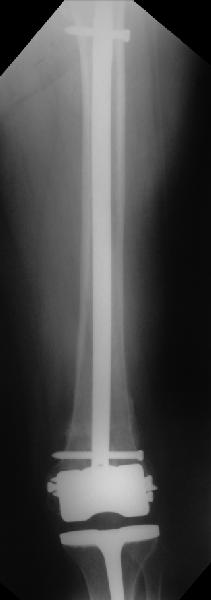

Оперирована по поводу перипротезного перелома н/з бедренной кости Оперирована по поводу перипротезного перелома н/з бедренной кости в ноябре 2010г.Диагноз:закрытый оскольчатый перелом бедренной кости в н/3 со смещением отломков, состояний после эндопротезирования коленного сустава от 2009г.Операция:артропластика коленного сустава, остеосинтез бедренной кости пластиной с угловой стабильностью.В июле операция по поводу несросшегося перелома н/3 бедренной кости,перелом пластины:взятие костного аутотрансплантата из гребня подвздошной кости, удаление пластины, костная аутопластика, остеосинтез бедренной кости пластиной с угловой стабильностью.На контрольном снимке от октября 2012г.- несросшийся перелом бедренной кости, ложный сустав.Что еще можно предпринять? Существуют ли методы лечения, кроме операционных? Поможет ли в данном случае гравитационная терапия7 Или ждать когда все-таки произойдет сращение или еще раз сломается пластина?И произойдет ли сращение вообще? Помогите советом.

Надо удалять пластину и либо вновь синтезировать пластиной, либо делать остеосинтез внутрикостным стержнем. Мы предпочли бы второй вариант. Стержень лучше вводить сверху. Запереть получается очень надежно. В отличие от пластины. стержень можно динамизировать, то есть за счет введения винта вверху в овальное отверстие можно оставить возможность для сближения фрагментов.

Добрый день. Оперировать не рекомендовали. После 3-х лет после операции- вот такая картина. Прокомментируйте пожалуйста снимки.

Снимок только в одной проекции, для более полной оценки ситуации надо и фас увидеть. И в первую очередь узнать о клиническом статусе - жалобы, ось, длина, амплитуда движений в колене, опоросопособность, потребность в дополнительной опоре?

В предыдущем сообщении к сожалению не удалось прикрепипь все снимки.Сейчас это исправляю.Высылаю все снимки в хронологии.

Жалобы следующие:

1.дискомфорт в области крепления пластины ( нужно найти определенное положение, иначе ощущается боль), 2.укорочения конечности в общем не ощущается,

3.колено в суставе полностью не сгибается, но котрактура была еще и до операции по эндопротезированию сустава, сгибалось только на 90 град. После перелома сгибается еще меньше.( Ну это уже не самая большая проблема по сравнению с несрастанием),

4.Хожу с дополнительной опорой на трость, полной нагрузки не даю, т.к. опасаюсь повторного перелома пластины.

По-поводу "оперировать не рекомендовали", имела ввиду своих лечащих врачей, говорили, что гарантии никакой дать не могут на сращение перелома."Ходишь и ходи" Будут проблемы - будем дальше думать.

Прошу Вас прокомментировать динамику. Почему пластина опустилась? И наблюдается ли все-таки сращение?